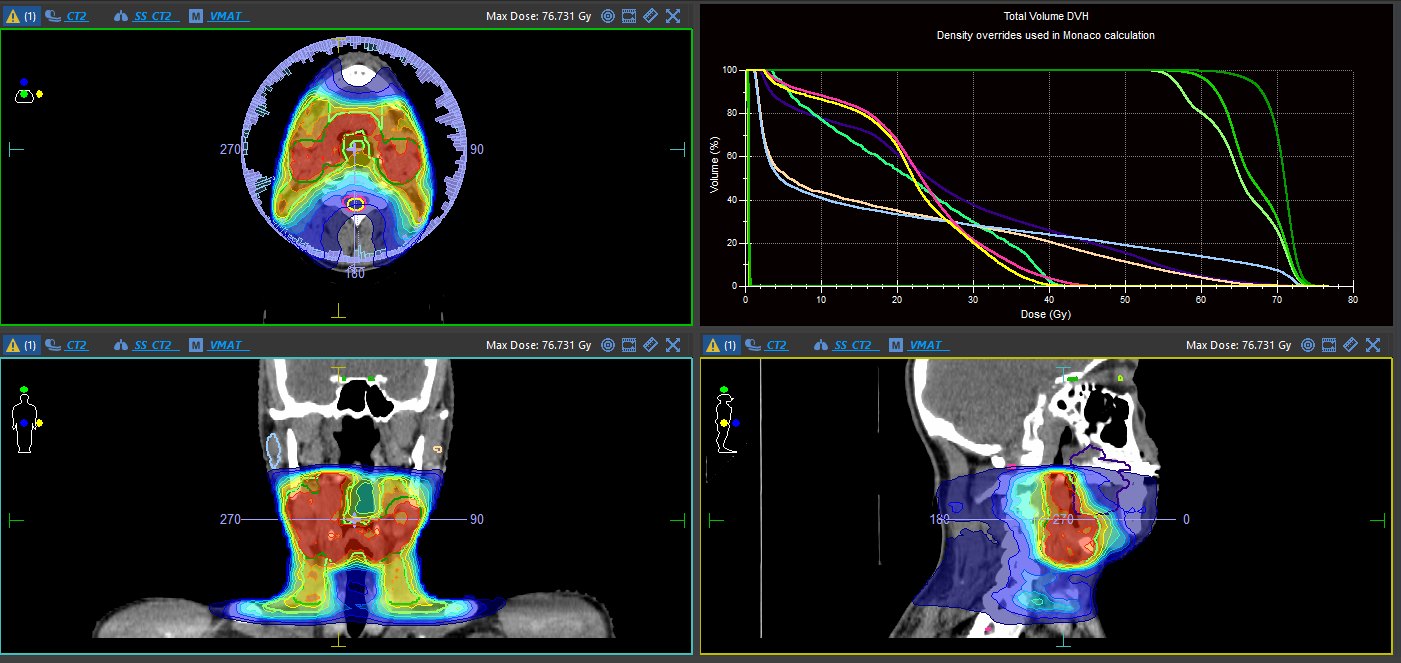

Лінійний прискорювач відкрив для лікарів Черкаського онкоцентру принципово нові можливості. Технологія дозволяє прицільно впливати на ракові клітини, знищуючи або зупиняючи ріст пухлин, але при цьому мінімізуючи шкоду для здорових тканин пацієнта. Про це йдеться в повідомленні Черкаського клінічного онкологічного центру.

За словами лікаря променевої терапії відділу радіаційної онкології, заступника медичного директора з радіології Сергія Михайлюка, можливість лікувати пацієнтів на новому лінійному прискорювачі — зовсім інший рівень. Це високотехнологічне й точне обладнання.

Завдяки плануванню й технічним можливостям фахівці можуть чітко обмежити, що опромінювати, а що не чіпати. І це дозволяє робити лікування безпечнішим, а також — ефективнішим, бо можна використовувати вищі дози за рахунок точності машини.